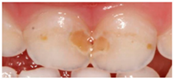

IMAGE 2![]() | Dental caries | 244 (68.0) |

| Enamel defects | 86 (24.0) | |

| No dental lesions | 8 (2.2) | |

| I do not know | 21 (5.8) | |